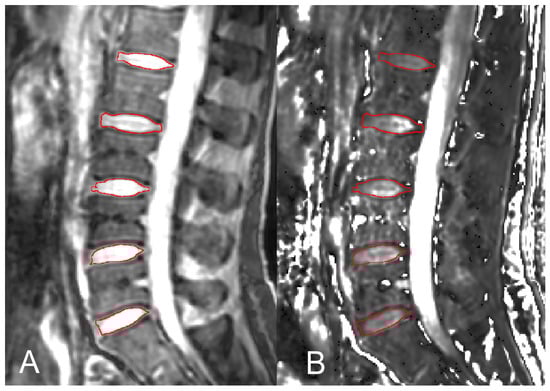

2.5. Region-of-Interest Setup and Measurements